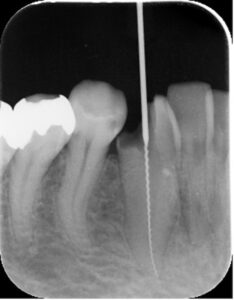

神経に達するほど大きな虫歯(中央の黒い部分)が出来ています。

細い針を用いて神経を除去していきます。

治療が終わった段階です。歯の根の先の方までしっかり詰め物をしています。